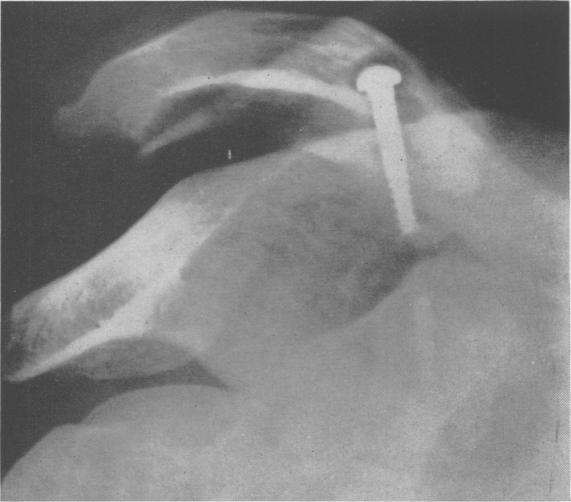

Acromioclavicular Dislocation: End-Results of Screw Suspension Treatment.

Ann Surg. 1948 Jan;127(1):98-111. doi: 10.1097/00000658-194801000-00009.